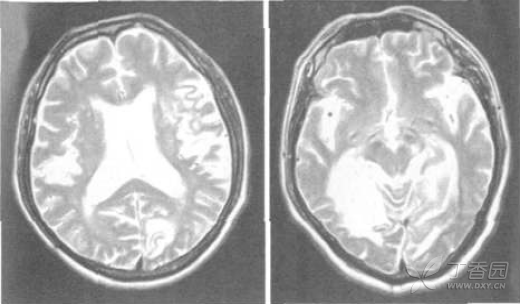

头颅CT示左侧大脑半球低密度影,右侧颞顶枕叶软化灶。诊断考虑定位于左侧大脑半球大脑中动脉与后动脉供血区,定性为缺血性脑血管病,首先考虑脑血栓形成。入院后血尿便常规、红细胞沉降率、血凝、血脂、血糖、电解质和肝肾功能等均正常。心电图示异常Q波。心脏超声示左室松弛性下降,颈动脉超声示双侧颈总动脉内膜毛糙。TCD示左侧大脑中动脉-颈内动脉分叉部伴杂音,脑动脉血流速度减低,弹性下降。头颅MRI示左侧基底节区和左侧颞枕叶急性脑梗死,右侧颞顶枕叶陈旧性脑梗死(图1)。视觉诱发电位结果正常。请眼科医师会诊,考虑患者色觉障碍为脑梗死引起,属后天性,查后天色觉障碍检查表(第V组)2004版:图99读为90,图60未能读,图266读为200,图928读为911,图68读为62,准确率为30%。